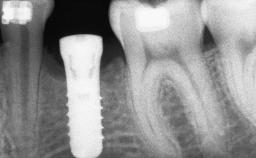

A 47-year-old Caucasian woman with a single-tooth edentulous space at the site of the left maxillary canine was referred for treatment. She had undergone traumatic extraction of this impacted canine several months before referral. Her chief complaint was the dissatisfying appearance of her smile. The patient desired a stable and esthetic rehabilitation of the site. Her dental history showed no evidence of periodontal disease or bruxism. She had no systemic diseases, was not taking any medications, and did not smoke. The extraoral examination revealed a high lip line and an inadequate soft-tissue volume at the defective canine site. Large black triangles were visible between the canine and its adjacent teeth.

| # of Implants | 1 |

| Bone Augmentation | Staged|Vertical |

| Augmentation Materials | Autogenous chips|Membrane |